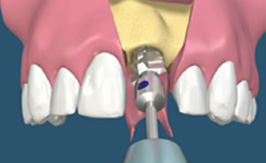

[치아발치]

[드릴링]

[발치 즉시 식립]